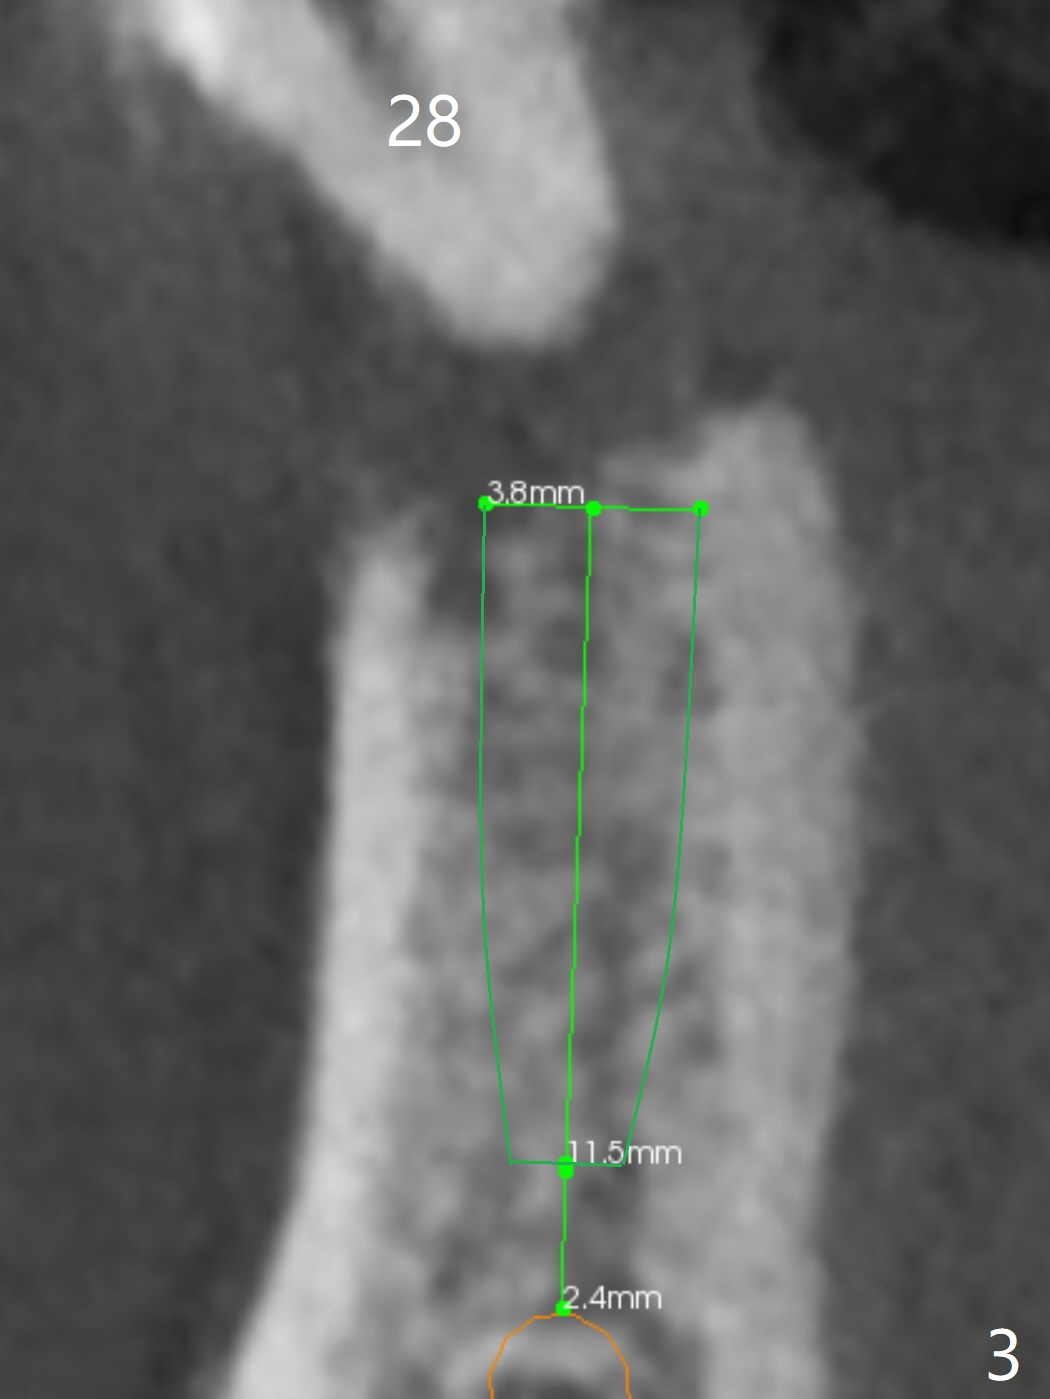

A 46-year-old man has finished upper implant placement (9-11 15 UR provisional) and wants to have lower anterior done (Long Cuff Wax up 2). The tooth #28 has exfoliated, while #22-27 FPD has mobility. It appears that the anchor tooth #22 has more severe periodontitis than that of #27. If the condition remains the same, section FPD between #22 and 23. Implants will be placed probably at #23, 26, 27 and 28. If both of the anchor teeth are non-salvageable, the possible implant will be at #22, one incisor, 27 and 28. In fact the patient requests an implant at #28.